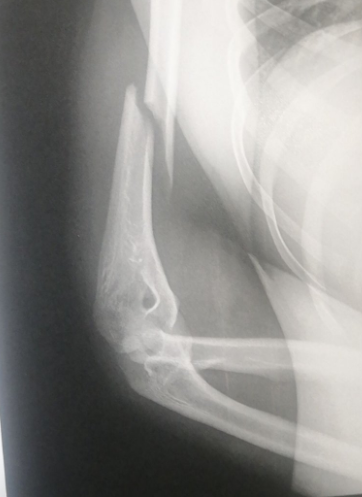

Notez mon bras coupé en 2 sur 10

qu'une fracture de l'humérus l'aw :(

ca date tout va bien maitenant a part le fait que j'ai une plaque en métal dans le bras :d) donc pas de platre https://image.noelshack.com/fichiers/2020/03/5/1579274578-really.png